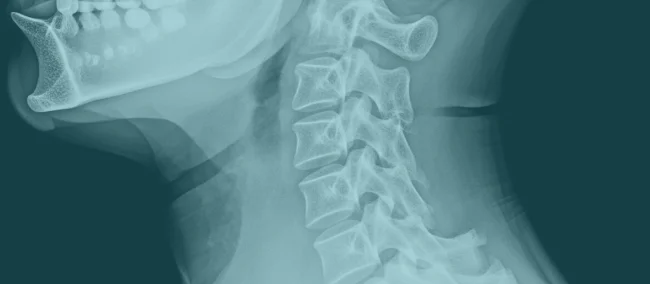

Servikal Grafi Hizmeti

Boyun sağlığınız için erken teşhis hayat kurtarır. Servikal radyoloji hizmetlerimizle, ağrı ve hareket kısıtlılıklarının nedenini hızlı ve güvenilir şekilde tespit ediyoruz.

Satem Mobil Sağlık olarak, yaşam kalitenizi etkileyebilecek ve hareket kabiliyetinizi kısıtlayabilecek servikal omurga problemlerini tespit etmek için servikal grafi hizmeti sunuyoruz.

1.Erken Teşhis: Servikal grafi, boyun ağrısı, omurga eğrilikleri, fıtık, kireçlenme ve diğer servikal omurga rahatsızlıklarının erken teşhisi için önemlidir. Erken teşhis, etkili tedavi ve yaşam kalitenizi yükseltme şansınızı artırır.